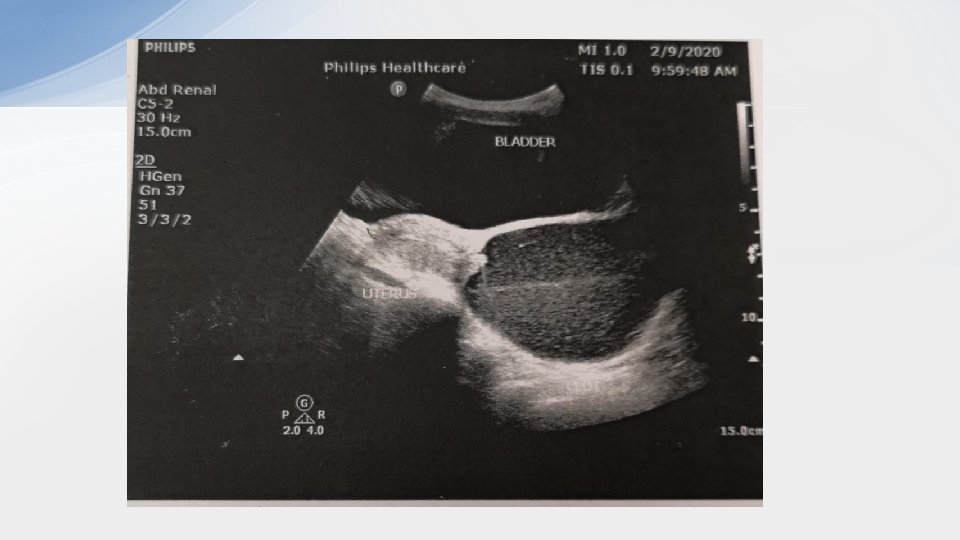

Case 4 • 42/F • S/F while chasing bus • Left shoulder injury

• 1. What are the x ray finding and diagnosis? – X ray AP: • humeral head displaced inferomedically to the glenoid fossa • Humerus in marked abduction – Inferior shoulder dislocation (luxatio erecta)

• 2. what are the 2 possible treatment methods in ED? – Traction and counter traction – 2 -step reduction • Convert the inferior dislocation into an anterior dislocation by pushing the proximal humerus anteriorly while pulling the elbow in a superior position • Adduct the arm • Use any reduction technique for anterior dislocation

• 3. What are the complications of the injury? –Brachial plexus nerve injury esp axillary nerve injury –Axillary artery thrombosis –Rotator cuff injury –Fracture of greater tuberosity of humerus, glenoid rim, acromion or clavicle –Glenolabral tear